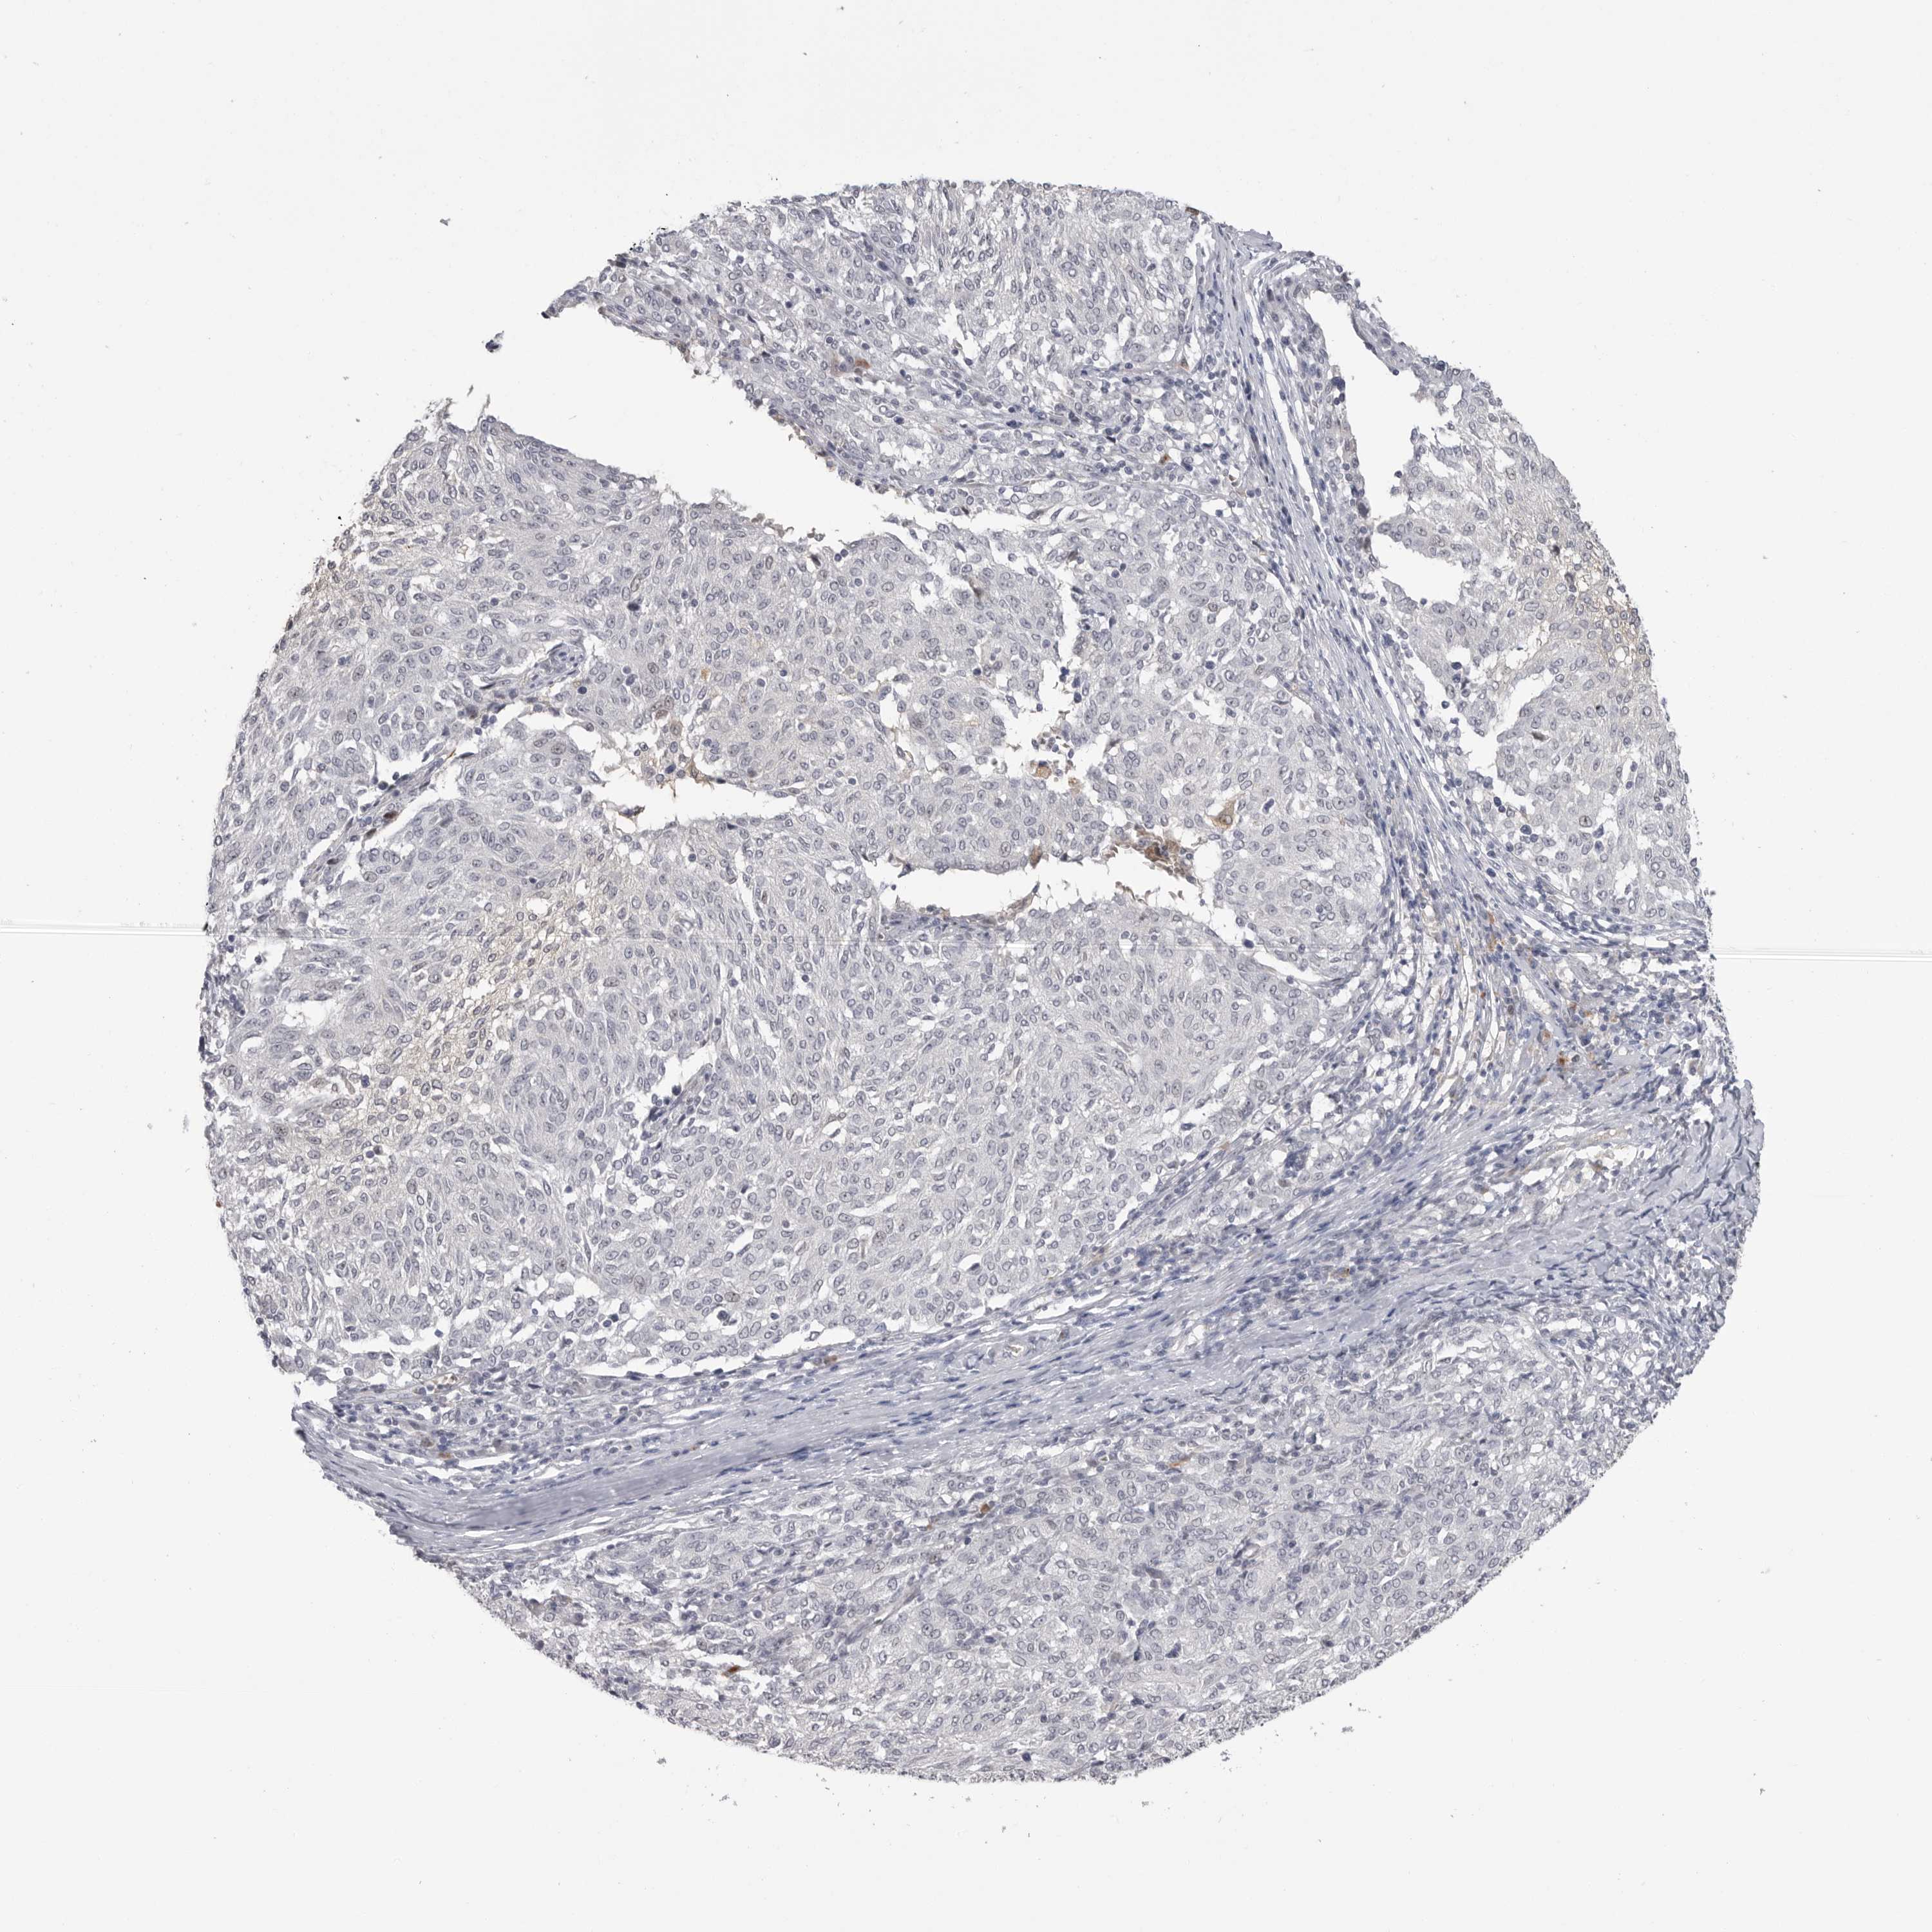

MELANOMA - Protein expressioni

A mouse-over function shows sample information and annotation data. Click on an image to view it in a full screen mode. Samples can be filtered based on level of antibody staining by selecting one or several of the following categories: high, medium, low and not detected. The assay and annotation is described here.

Note that samples used for immunohistochemistry by the Human Protein Atlas do not correspond to samples in the TCGA dataset.

Antibody stainingi

Antibody staining in the annotated cell types in the current human tissue is reported as not detected, low, medium, or high, based on conventional immunohistochemistry profiling in selected tissues. This score is based on the combination of the staining intensity and fraction of stained cells.

Each image is clickable and will lead to virtual microscopy that enables deeper exploration of all samples and also displays staining intensity scores, fraction scores and subcellular localization as well as patient and tissue information for each sample.

Antibody HPA025925

Staining

High

Medium

Low

Not detected

Intensity

Strong

Moderate

Weak

Negative

Quantity

>75%

75%-25%

<25%

None

Location

Nuclear

Cytoplasmic/membranous

Cytoplasmic/membranous,nuclear

Malignant melanoma, NOS

Malignant melanoma, Metastatic site